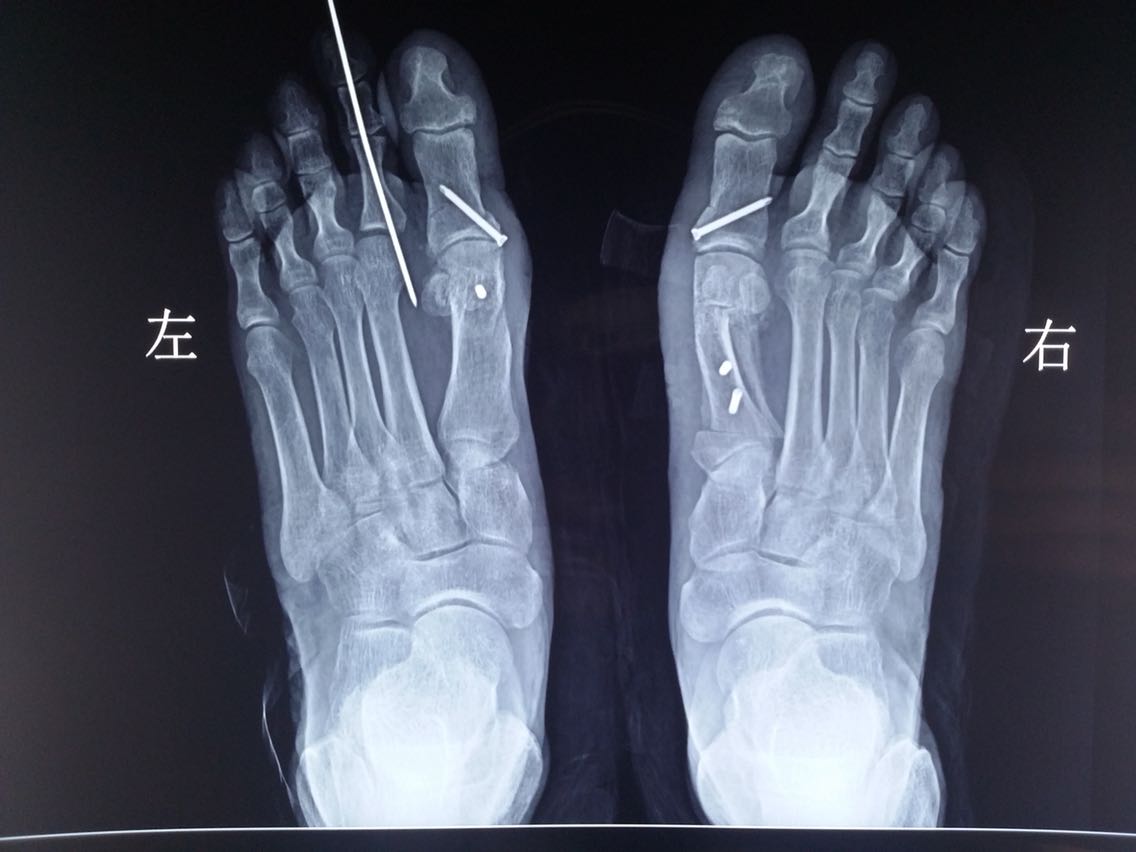

主诉:双足第一趾外翻畸形10余年。 病史:患者F/55,自述双足无明显诱因出现第一趾外翻畸形10余年,长时间行走或工作劳累后出现疼痛,近2年来症状加重。

查体及辅助检查:双足第一趾重度外翻畸形,第一趾长轴与第一跖骨长轴夹角>25°,第一、二跖骨头夹角>9°。

诊断:双足拇外翻畸形 治疗:截骨矫形修复术